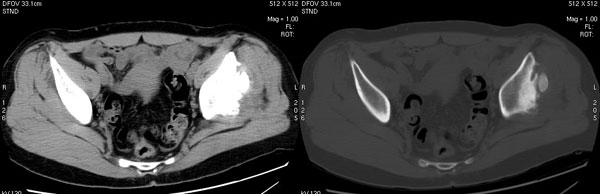

以下是引用jiajie在2006-7-14 17:19:00的发言:[br]ct所见:双侧髋关节不对称,左侧关节间隙变窄,关节面毛糙。左侧股骨头变形、无明显变小,前上缘与髋臼融合,融合处骨质明显增生硬化,并见数个小囊变影。股骨头下端与股骨颈交界部见囊样变,邻近肌肉内见囊样密度减低区,ct值24hu。右侧髋关节形态未见异常。[br][br]ct诊断:左侧髋关节结核可能,请结合临床资料进一步分析。

以下是引用lihuuuu在2006-12-5 10:14:00的发言:[br]定位像示:左侧髋臼变浅,倾斜度加大,髋臼外上缘呈波浪状不规则,骨质增生硬化,髋关节上缘间隙明显变窄,股骨头向外上轻度移位。轴位像示:左侧股骨头变形,前上缘与髋臼融合,融合处骨质明显增生硬化,并见数个小囊变影。股骨头下端与股骨颈交界部见囊样变,邻近肌肉内见密度减低区,ct值24hu,内缘见弧形高密度钙化影。右侧髋关节形态未见异常。[br]ct诊断:左侧髋臼发育不良[br] 左侧股骨头缺血性坏死[br] 左侧肌肉内低密度影伴有高密度钙化-考虑早期骨化性肌炎[br] [br]“我认为在描述上已经写了肌肉部分,印象诊断里应该写主见”[br]